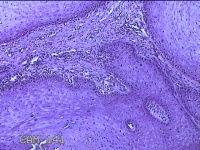

性别

男

年龄

26岁

临床诊断

面部肿物

一般病史

左侧面部无痛性肿物一月余。

标本名称

左侧面部肿物

大体所见

灰白暗红色肿物0.7x0.3x0.2cm一个,表面糜烂。

图2